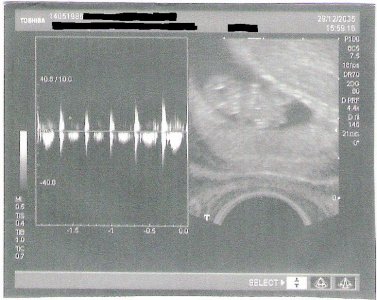

Black_Magic - Bild 2